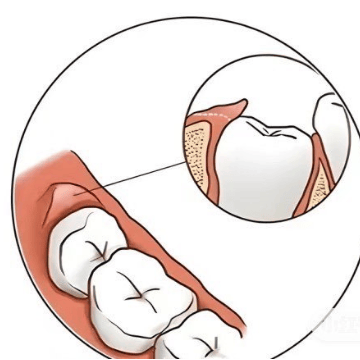

水平型

咀嚼时食物碎块由于舌及颊的力量,自舌侧或颊侧横向压入牙间隙内,多见于牙龈萎缩的患者,对牙龈组织损害相对较轻,食物虽容易被清除,但却很难根治。

水平性嵌塞的可能原因

如果两牙之间的牙龈乳头退缩等原因造成两牙之间下方出现空隙,食物易在唇、颊及舌部的力量下水平进入此间隙,造成水平性食物嵌塞。